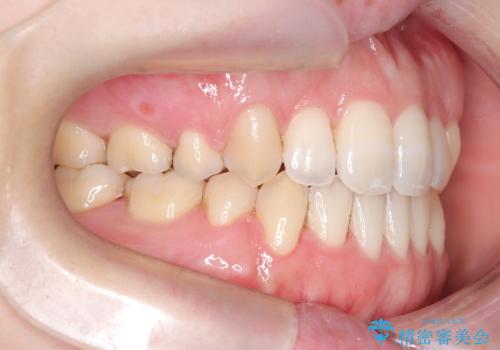

治療後は、前歯の位置や噛み合わせが整い、見た目も機能面も大きく改善されました。きれいな歯並びを得ることができ、患者様にも非常に満足していただけました。

抜歯によって確保したスペースを活用し、効率的に歯列を整えました。前歯のガタガタと八重歯が解消され、自然で美しい仕上がりを実現しました。